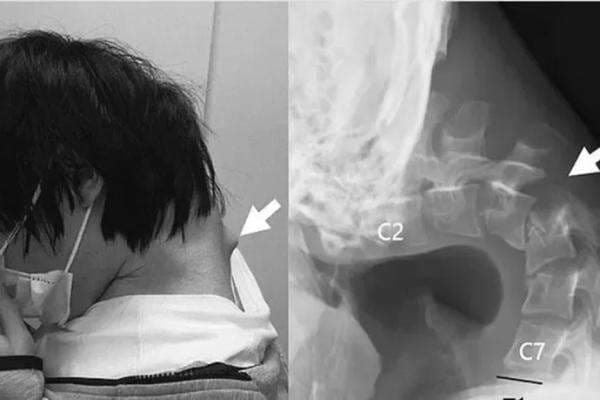

Seorang pria muda asal Jepang mengalami kondisi medis langka setelah kecanduan bermain game di HP selama bertahun-tahun. Akibat terlalu lama menunduk menatap layar, lehernya membengkok dan otot-ototnya kehilangan kemampuan menopang kepala, yang membuatnya tidak mampu mengangkat kepala sendiri.

Pria 25 tahun itu kemudian didiagnosis menderita dropped head syndrome atau sindrom kepala terkulai, kondisi langka yang umumnya berkaitan dengan gangguan neuromuskular. Tapi dalam kasus ini disebabkan oleh postur tubuh yang buruk dalam waktu lama.

Sejak itu, ia mengurung diri di kamar dan menghabiskan sebagian besar waktunya bermain ponsel dalam posisi menunduk. Kebiasaan tersebut menyebabkan tonjolan besar terbentuk di bagian belakang leher.

Di mana hasil pemeriksaan menunjukkan adanya distorsi pada tulang belakang leher, peregangan abnormal, serta jaringan parut di area tulang belakang bagian atas. Awalnya, tim medis mencoba menggunakan penyangga leher sebagai solusi non-bedah.